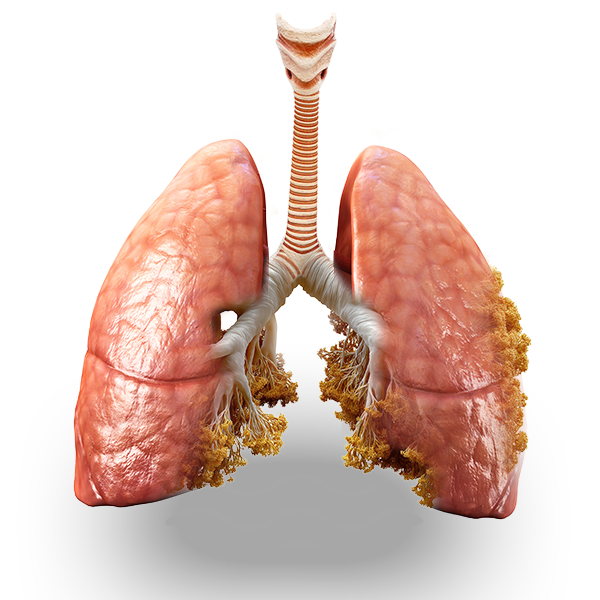

WEAKENED FROM THE INSIDE

Vaping can damage your body’s natural ability to defend itself.

Every day we learn about new ways that vaping can be harmful to our bodies. Studies have found cancer-causing chemicals in vape juice, like pulegone, AND vapor, like formaldehyde.

Inhale at Your Own Risk

Whether you vape THC or nicotine, it doesn’t matter. There’s no such thing as a safe vape. ALL have been associated with serious health risks.